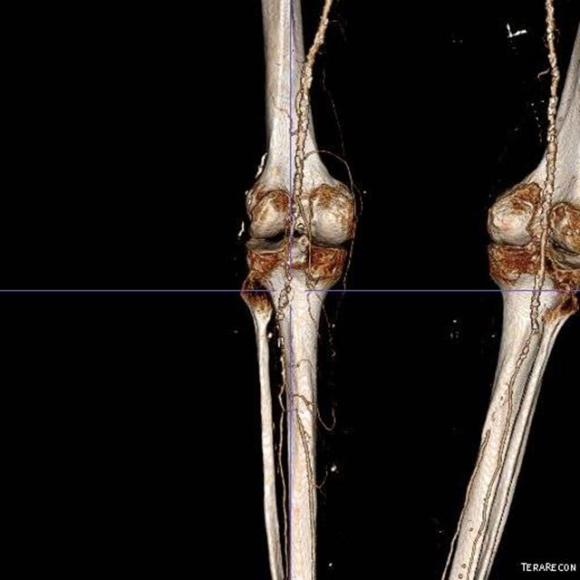

The patient is a gentleman from out of state who had called about problems he was having with walking and with leg ulcers that wouldn’t heal. He is in his seventies and has a pacemaker for an arrhythmia for which he was on Xarelto. He also had type II diabetes. He had bilateral lower extremity deep venous thromboses 6 years prior requiring IVC filter placement. The filter occluded, and it resulted in sudden sharp and debilitating pain in both legs with walking short distances -some days only 50 paces.He described it as an unbearable pain in calves and thighs that felt like his legs were going to burst. He also had ulcers on his legs that would heal with ministration but soon recur. This was all despite being quite active, with regular workouts, and being fit. He was compliant with compression. He sent a CT scan done last year (below).

It showed an Optease retrievable vena cava filter that was occluded and the iliac systems bilaterally (right above and left below) were chronically occluded with patent vena cava above and femoral confluences bilaterally below.

Examination revealed a fit and trim man in his 70’s in no apparent distress. He had bilateral leg edema that was moderate with small superficial and tender ulcers of the right posterior distal calf. Pulses were normal. He was taken to our hybrid suite and venography from femoral vein access in the proximal thigh in the supine position revealed his right and left iliac venous systems to be occluded (below figures).